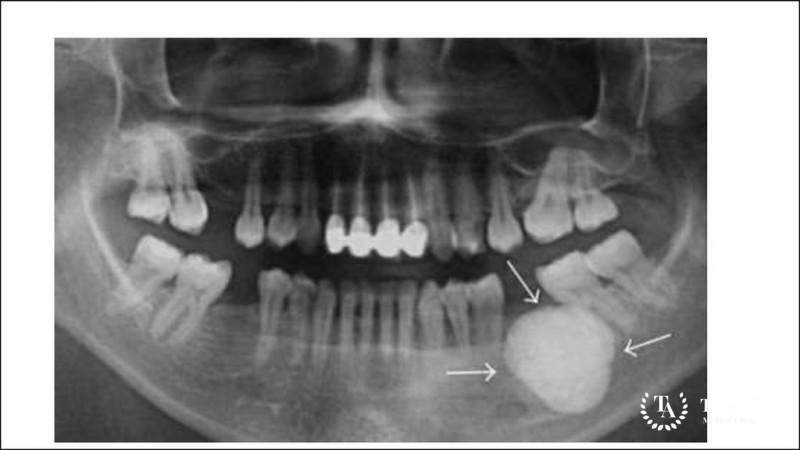

Гигантоклеточная опухоль кости (остеобластокластома, остеокластома) – это доброкачественная опухоль костной ткани, которая склонна к местно-деструктивному течению, то есть новообразование по […]